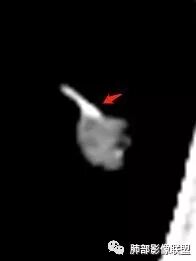

血管到底有没有破坏?

云荼:

血管贴边,但没有明显压迫征象。明显强化。局部膨隆,毛刺,分叶。

胸膜牵拉,这些都支持恶性

请问南边老师,这个进入结节的血管算增粗吗?

南边:

稍增粗

恶性征像,胸膜牵拉,浅分叶,毛刺,增强强化明显,净增超25hu。血管边缘模糊串珠样改变。